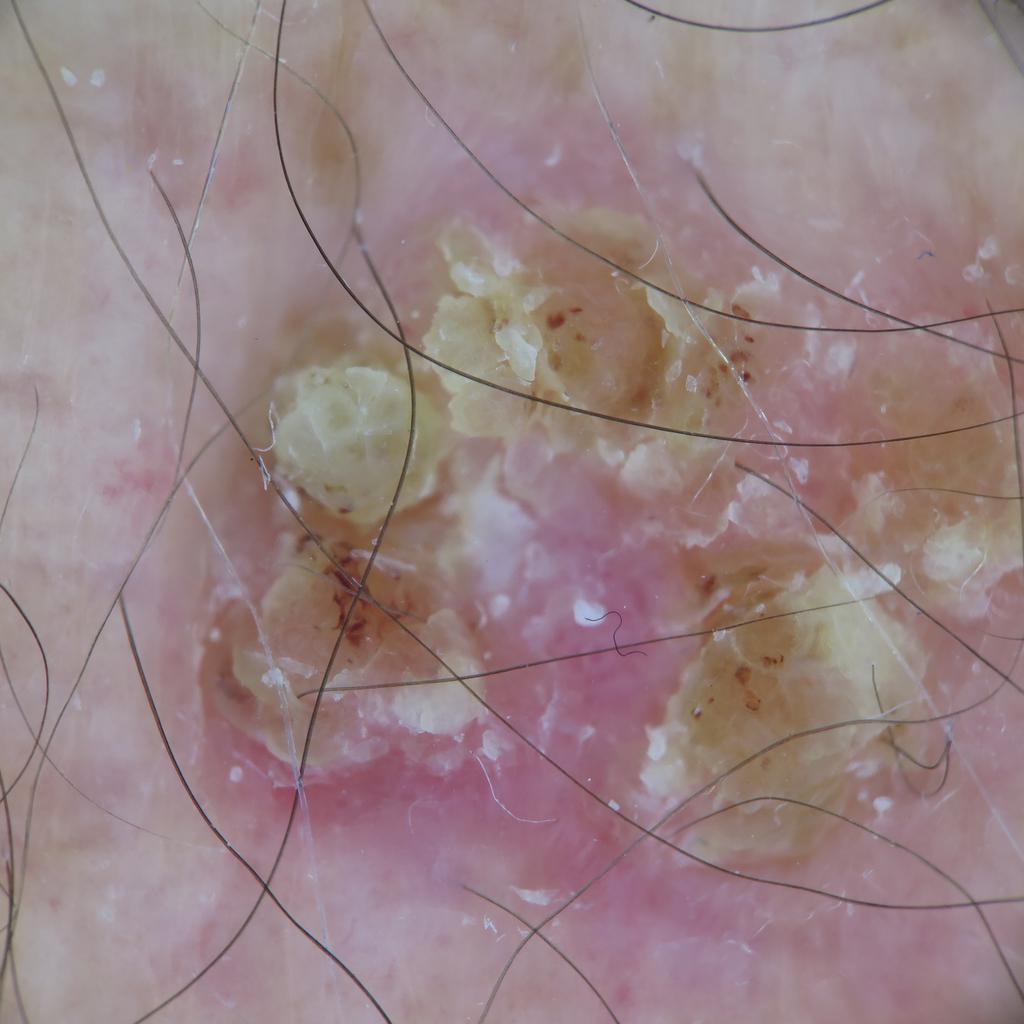

A Large Squamous Cell Carcinoma

Deborah S. Sarnoff, MD

Before being admitted to an assisted living facility, an elderly widow was required to have a thorough physical. The doctor (and her adult children who had not seen her undressed in years), were shocked to see a large, raised open wound on her left shoulder and back. For years, she had been covering it and hiding it under clothes. She didn’t want to rock the boat or make a fuss. The lesion (top photo) turned out to be a large SCC, the second most common type of skin cancer. The tumor required extensive surgery followed by radiation. The patient was extremely lucky: Her cancer was eliminated, and Dr. Sarnoff’s business partner and husband Robert H. Gotkin, MD, expertly closed the wound (bottom photo). Dr. Sarnoff strongly advocates robust treatment for elderly people with skin cancer. The earlier it is diagnosed, the less onerous the treatment, and it can make a huge difference in a person’s quality of life.